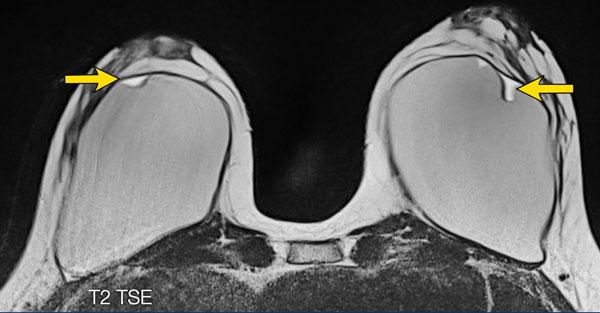

Bệnh nhân nữ này có vỡ túi ngoài bao xơ bên phải với silicone nằm ngoài bao xơ dày (mũi tên trắng).

Ở vú trái có vỡ túi trong bao xơ được biểu hiện bằng đường dưới bao xơ với silicone ở cả hai phía của đường này (mũi tên vàng).